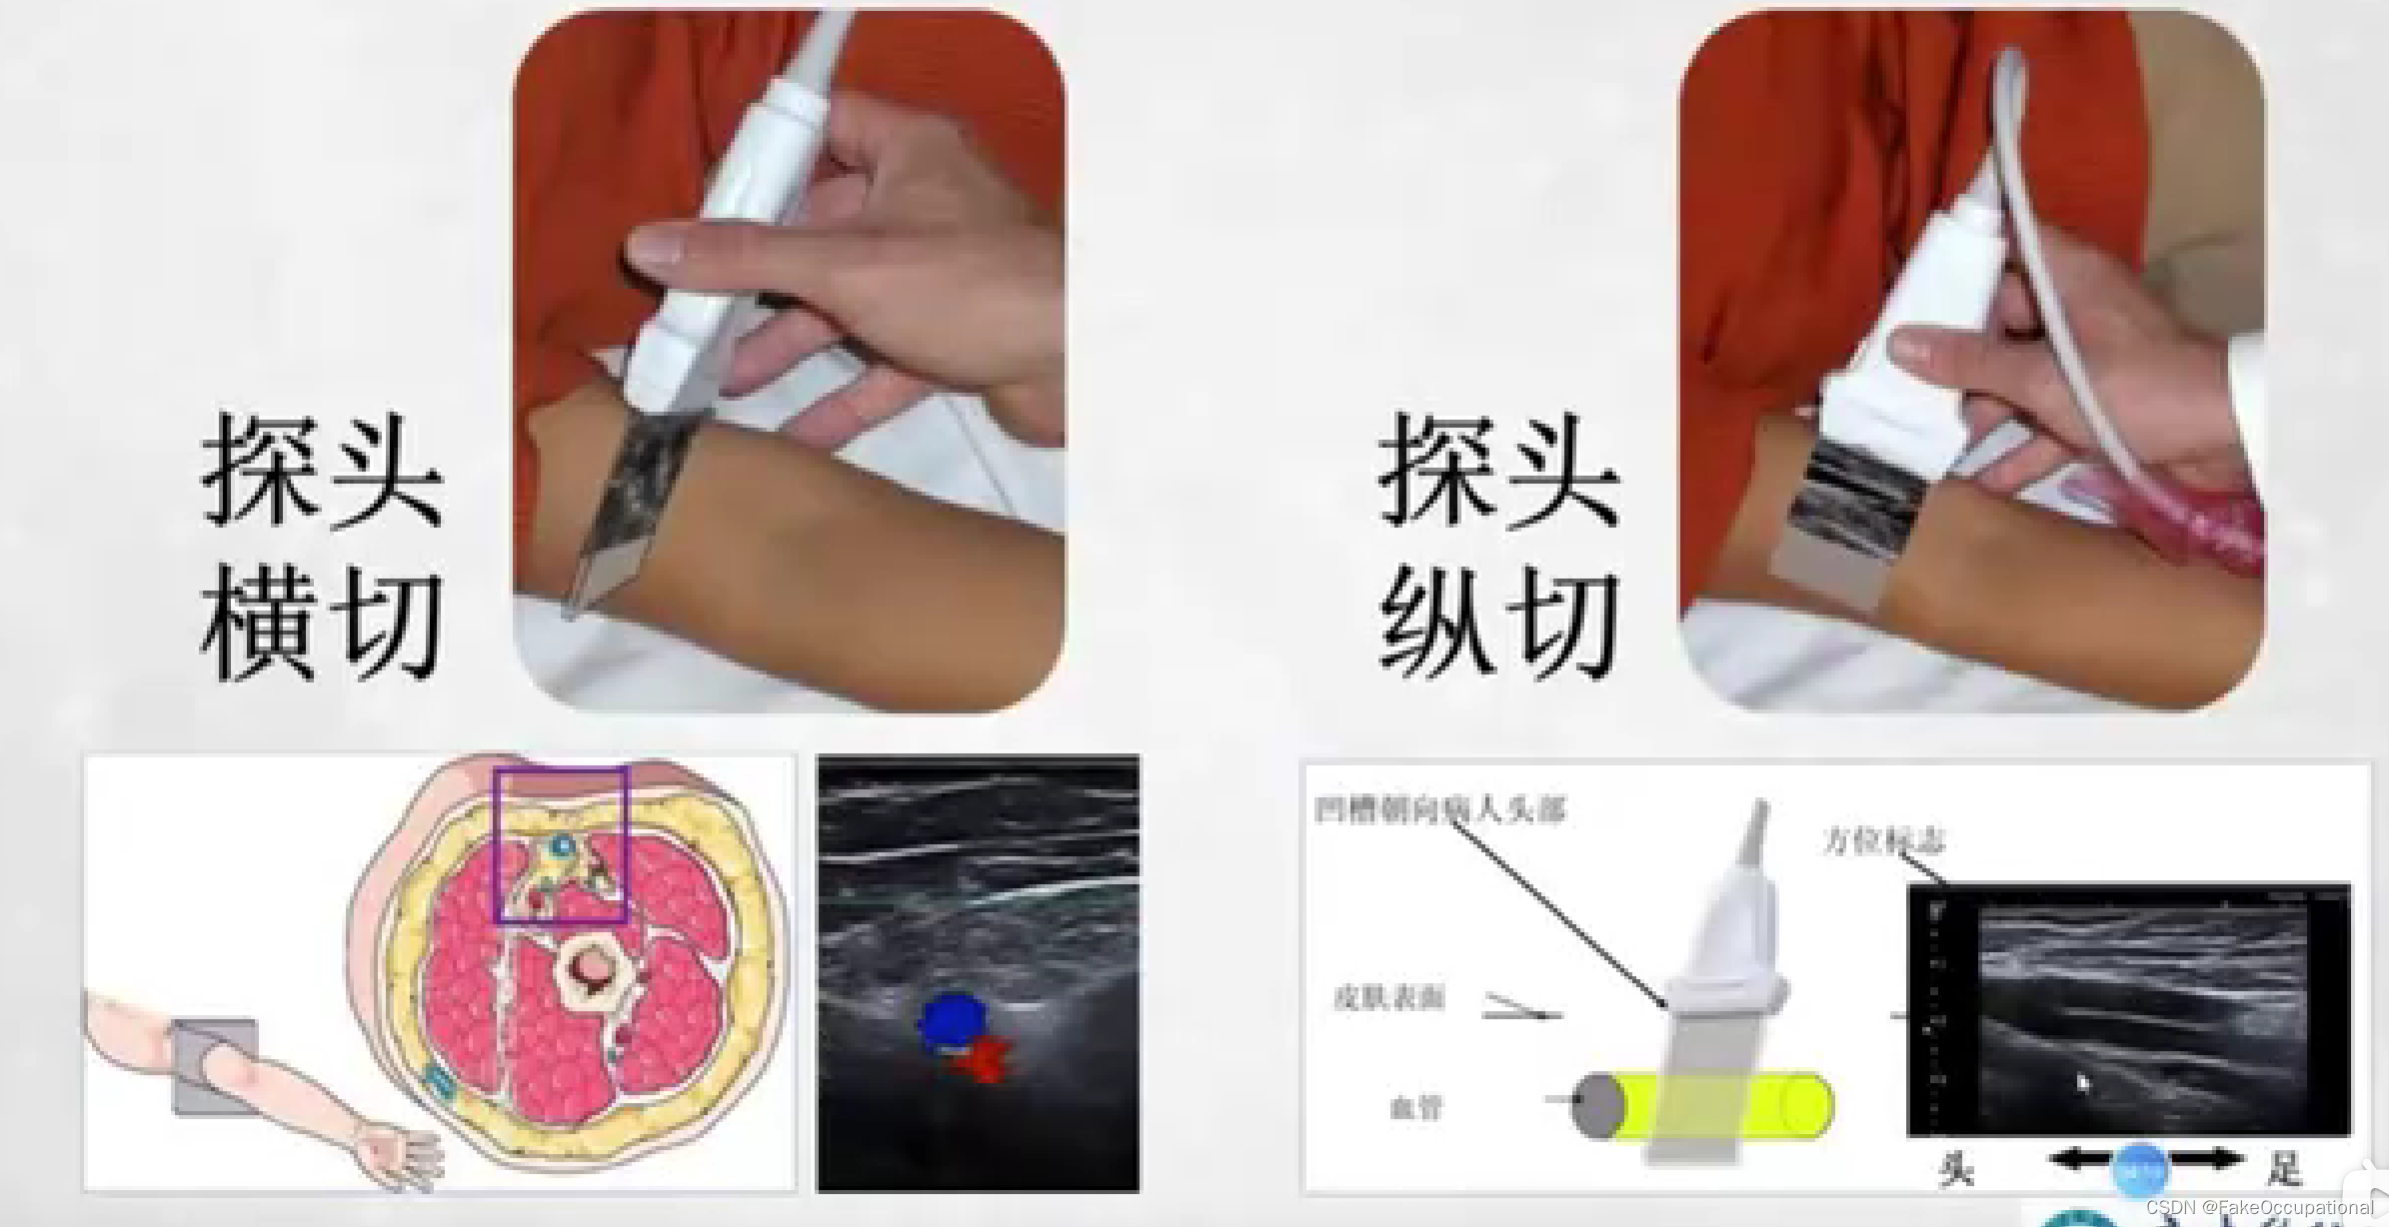

- 探头上是有方位标记点的,显示器中方位点在左侧。标准方向放置后,患者的右侧应该出现在显示器的左侧。探头一侧的探头方向标记应面向患者的右侧(如果探头纵向定向,则朝向头侧),并且超声监视器上的标记点位于超声监视器的左上角。

- 图中前后指的是深度